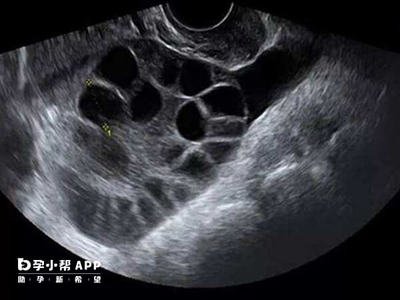

- 超声检查显示双侧卵巢呈多囊样改变(即每侧卵巢中2~9mm的小卵泡数量≥12个)

- 多囊样卵巢(PCO) 是指超声下观察到卵巢体积增大、小卵泡增多的现象,但不一定伴有其他PCOS的症状。